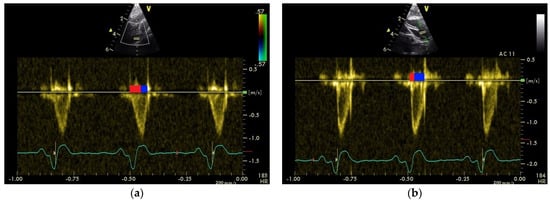

3.3. Influence of Anaesthesia with Isoflurane on the Shape of the PAFP and AOFP